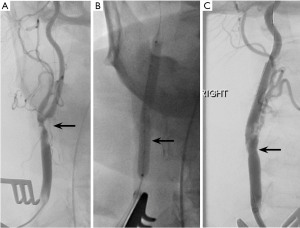

A 73-year-old female with asymptomatic, severe left internal carotid artery (ICA) stenosis diagnosed based on carotid duplex ultrasound (DUS) [ICA peak systolic velocity (PSV) 419 cm/sec, ICA/common carotid artery (CCA) ratio of 7.2] and confirmed on computed tomography angiography (CTA) (Figure 1A). The lesion was 21 mm long, and a circumferential calcification thickness of 4 mm was evaluated for possible intervention. The CCA was free from atherosclerotic disease. She also had asymptomatic, moderate right ICA stenosis. Cardiovascular risk factors included smoking (former), obesity [body mass index (BMI) =37 kg/m2], history of myocardial infarction, congestive heart failure (CHF) [ejection fraction (EF) 30%], chronic obstructive pulmonary disease (COPD) and chronic kidney disease stage (CKD 3a). Due to extensive comorbidities, the decision was made to treat her with minimally invasive left trans-carotid ICA IVL, followed by stenting. The procedure was conducted through a 3 cm left supraclavicular incision. Through the 8 Fr ENROUTE sheath (Silk Road Medical Inc., California), an intraoperative angiogram was obtained, demonstrating 85% stenosis of the ICA (Figure 1B). After the CCA was clamped, under roadmap assistance, a 0.014 wire was advanced beyond the lesion. The lesion was pre-dilated with a 5 mm shockwave balloon with good luminal gain (4 cycles, 30 seconds each), followed by the deployment of an 8 mm × 40 mm PRECISE stent (Cordis, Miami Lakes, Florida). Flow reversal was then allowed for 2 min. Completion angiography was performed after the removal of the proximal clamp, which revealed no dissection, contrast extravasation, or residual stenosis (Figure 1C). Total flow reversal time was 12 minutes. At six-month follow-up, the patient remained neurologically intact, and the carotid DUS showed widely patent stent (ICA PSV 127 cm/sec, ICA/CCA ratio of 2.3).